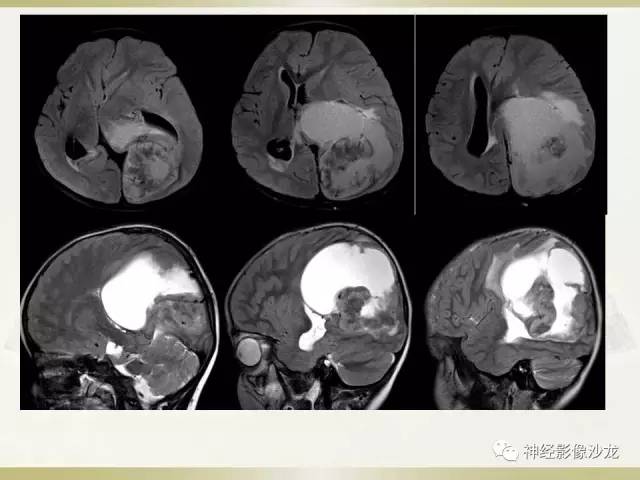

这里应该是侧脑室后角

侧脑室三角区受压

感觉有钙化,而且太大了,恶性水肿应该症状更明显了

水肿不够,钙化交成熟

室管膜瘤

影像挺符合

儿童,侧脑室三角区旁、囊变、钙化、出血,下次见到首先考虑啊

@神经义工周刚-黄冈市医影像科 pnet还是实性多,幕上室管膜瘤囊性为主,在侧脑室周围。dwi高可能提示间变